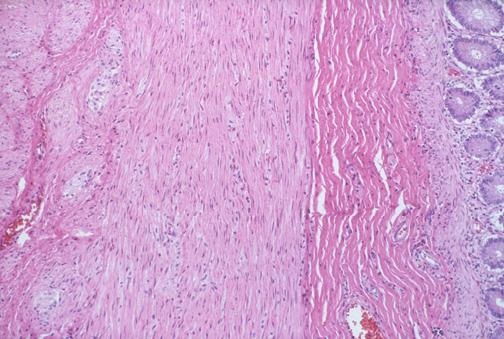

| The myenteric plexuses with ganglia are seen here in the colon. These myenteric (Auerbach's) plexuses are located between the outer longitudinal and the inner circular muscle layers. The mucosa is seen at the far right, beneath which is a thin muscularis mucosa , and beneath that a submucosa. |